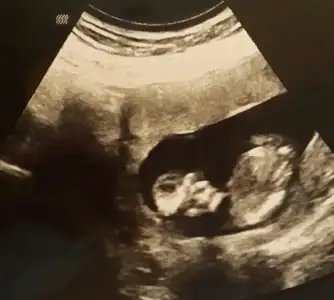

dr soylemeden siz gorun genital nub teorisi ( bebegin cinsiyeti)

Bu bebiste kardeşim in tahmin de bulunabilir misiniz

benimki 12+5 dr kiz gibi ama yanilma olasiligim yuksek dedi. bir ay sonra randevumuz o zaman kesin ogrenirz cok sagol cevabin icin